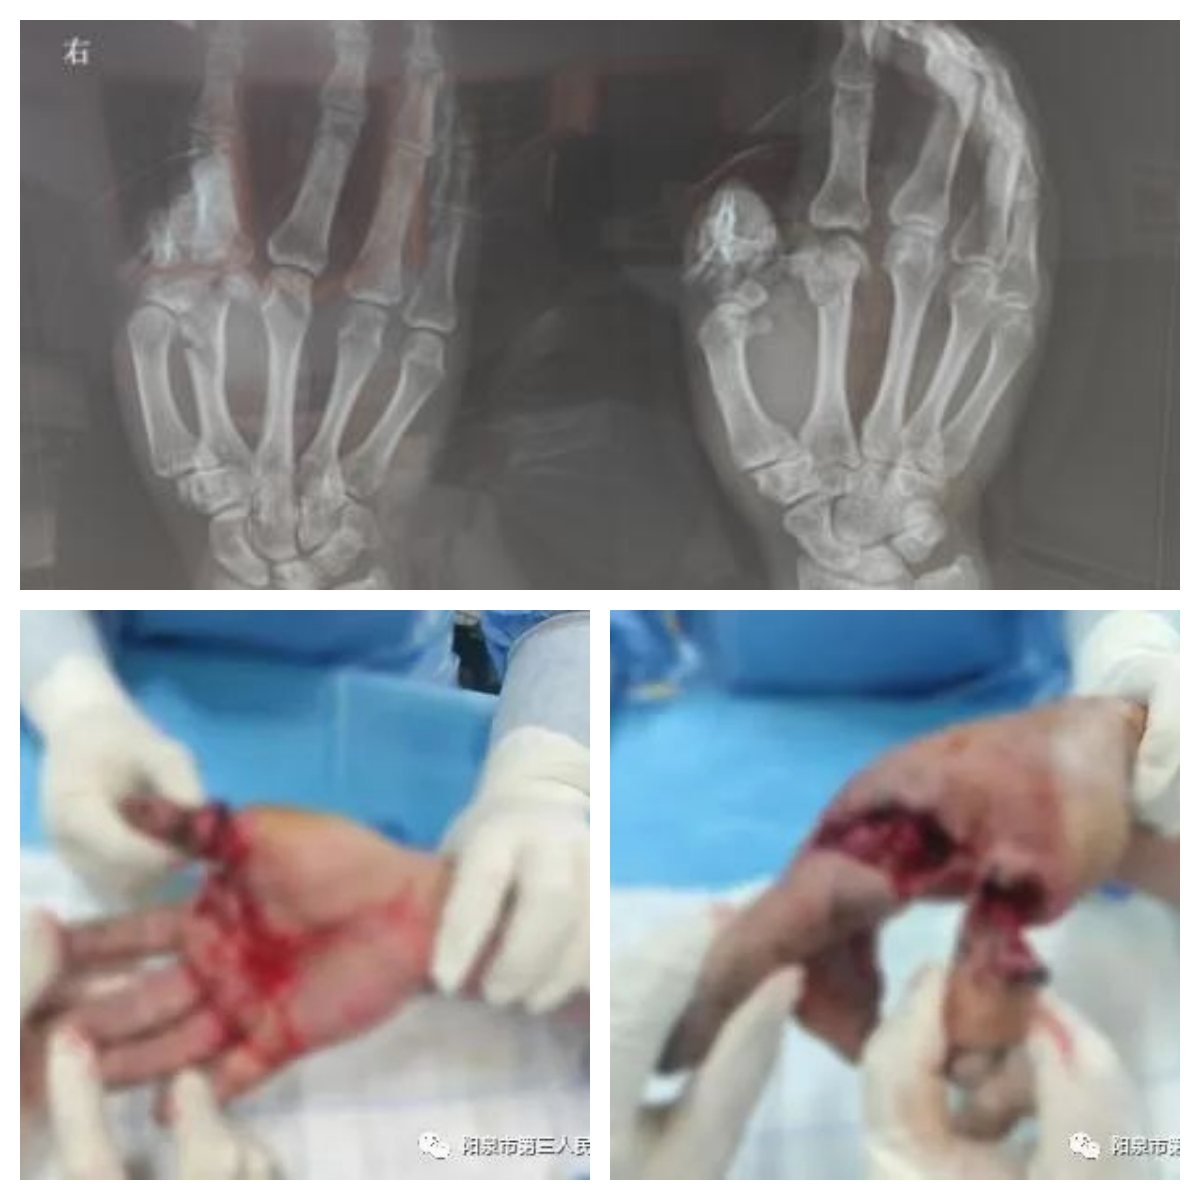

患者,男性,51岁,在单位工作时不慎被石头砸伤右手,致拇指完全离断、第2掌骨粉碎性骨折,紧急到院就诊。值班医师崔爽爽接诊,查看伤情发现,患者右手拇指于近节近端完全离断,仅屈指深肌腱、双侧指神经及桡侧0.5cm表皮相连,离断指体无血运,指体呈苍白色;第2掌骨粉碎性骨折。离断指体的血管、神经已经非常纤细且损伤严重,再植的难度很大。

手外科团队迅速完成术前检查及准备,展开手术。经清创、探查,医生发现,患者离断的拇指近节指骨呈粉碎性,指动脉完全断裂且栓塞,局部软组织挫灭、污染严重。经研判后,团队将患者拇指骨折断端进行短缩修整,使用克氏针固定断指,在显微镜下吻合手指动静脉并修复伸肌腱。手术历时5小时完成。术后,患者再植拇指皮肤色泽红润,血运好。